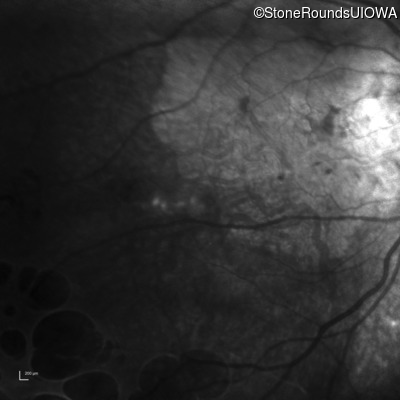

Infrared Fundus Photograph - Right - 20/100 +1

Exemplar